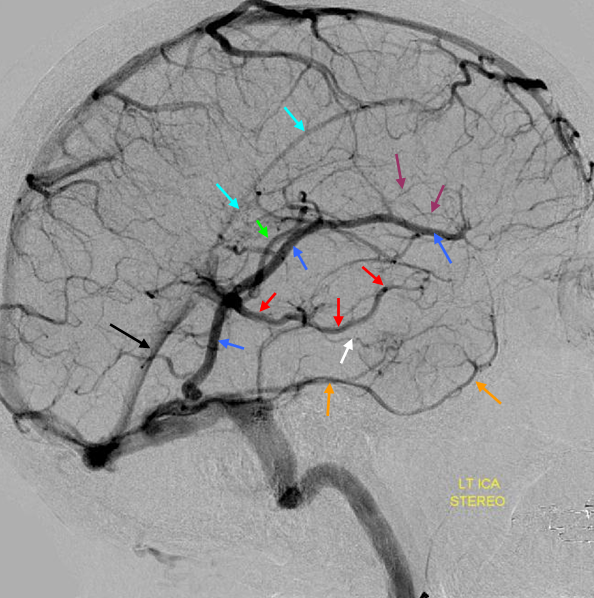

The general neurosurgical fact that the anterior third of the superior sagittal sinus can be safely sacrificed is true almost all the time. When it is not, consequences can be catastrophic. Normally, few veins drain into the anterior 3rd of the SSS, and these usually have collaterals. However, occasionally a large frontal or sylvian vein happens to drain anteriorly. Taking this sinus means risking a venous infarct. Here is an extreme example of dominant inferior left frontal vein draining into the anterior third of the frontal sinus, on MRI. Case courtesy Dr. Howard Riina

Angio is much easier to appreciate. It is well to learn how to spot these veins on MR or CT, as most patients don’t get presurgical angiography for nonvascular lesion

Another compensation for hypoplasia of the SSS is shift of superficial drainage into the deep venous system via the medullary veins draining into the internal cerebral veins. Courtesy Dr. Gopi Nayak. There is hypoplasia of the Superior Sagittal Sinus.

As one way of compensation for this superficial venous system deficiency, there is more venous drainage routed to the deep system. Amazing images of deep medullary/transverse venous prominence — completely nonpathologic, simply reflecting a shift of drainage equilibrium towards the deep venous system

Some arrows. Open white arrows — septal veins on the medial aspect of frontal horn. Thick white arrows — longitudinal caudate venous arcade. Black arrow — direct lateral vein, prominent because of hypoplasia of the posterior segment of the left longitudinal caudate vein. Thin white arrows are transverse/ medullary veins